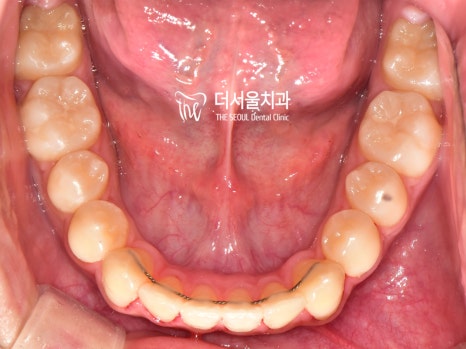

『결과』

전과는 달리 벌어졌던 이 사이도

긴밀하게 붙어 있는 것이 확인되었으며

툭 튀어나와 있던 돌출입도 개선이 되었습니다.